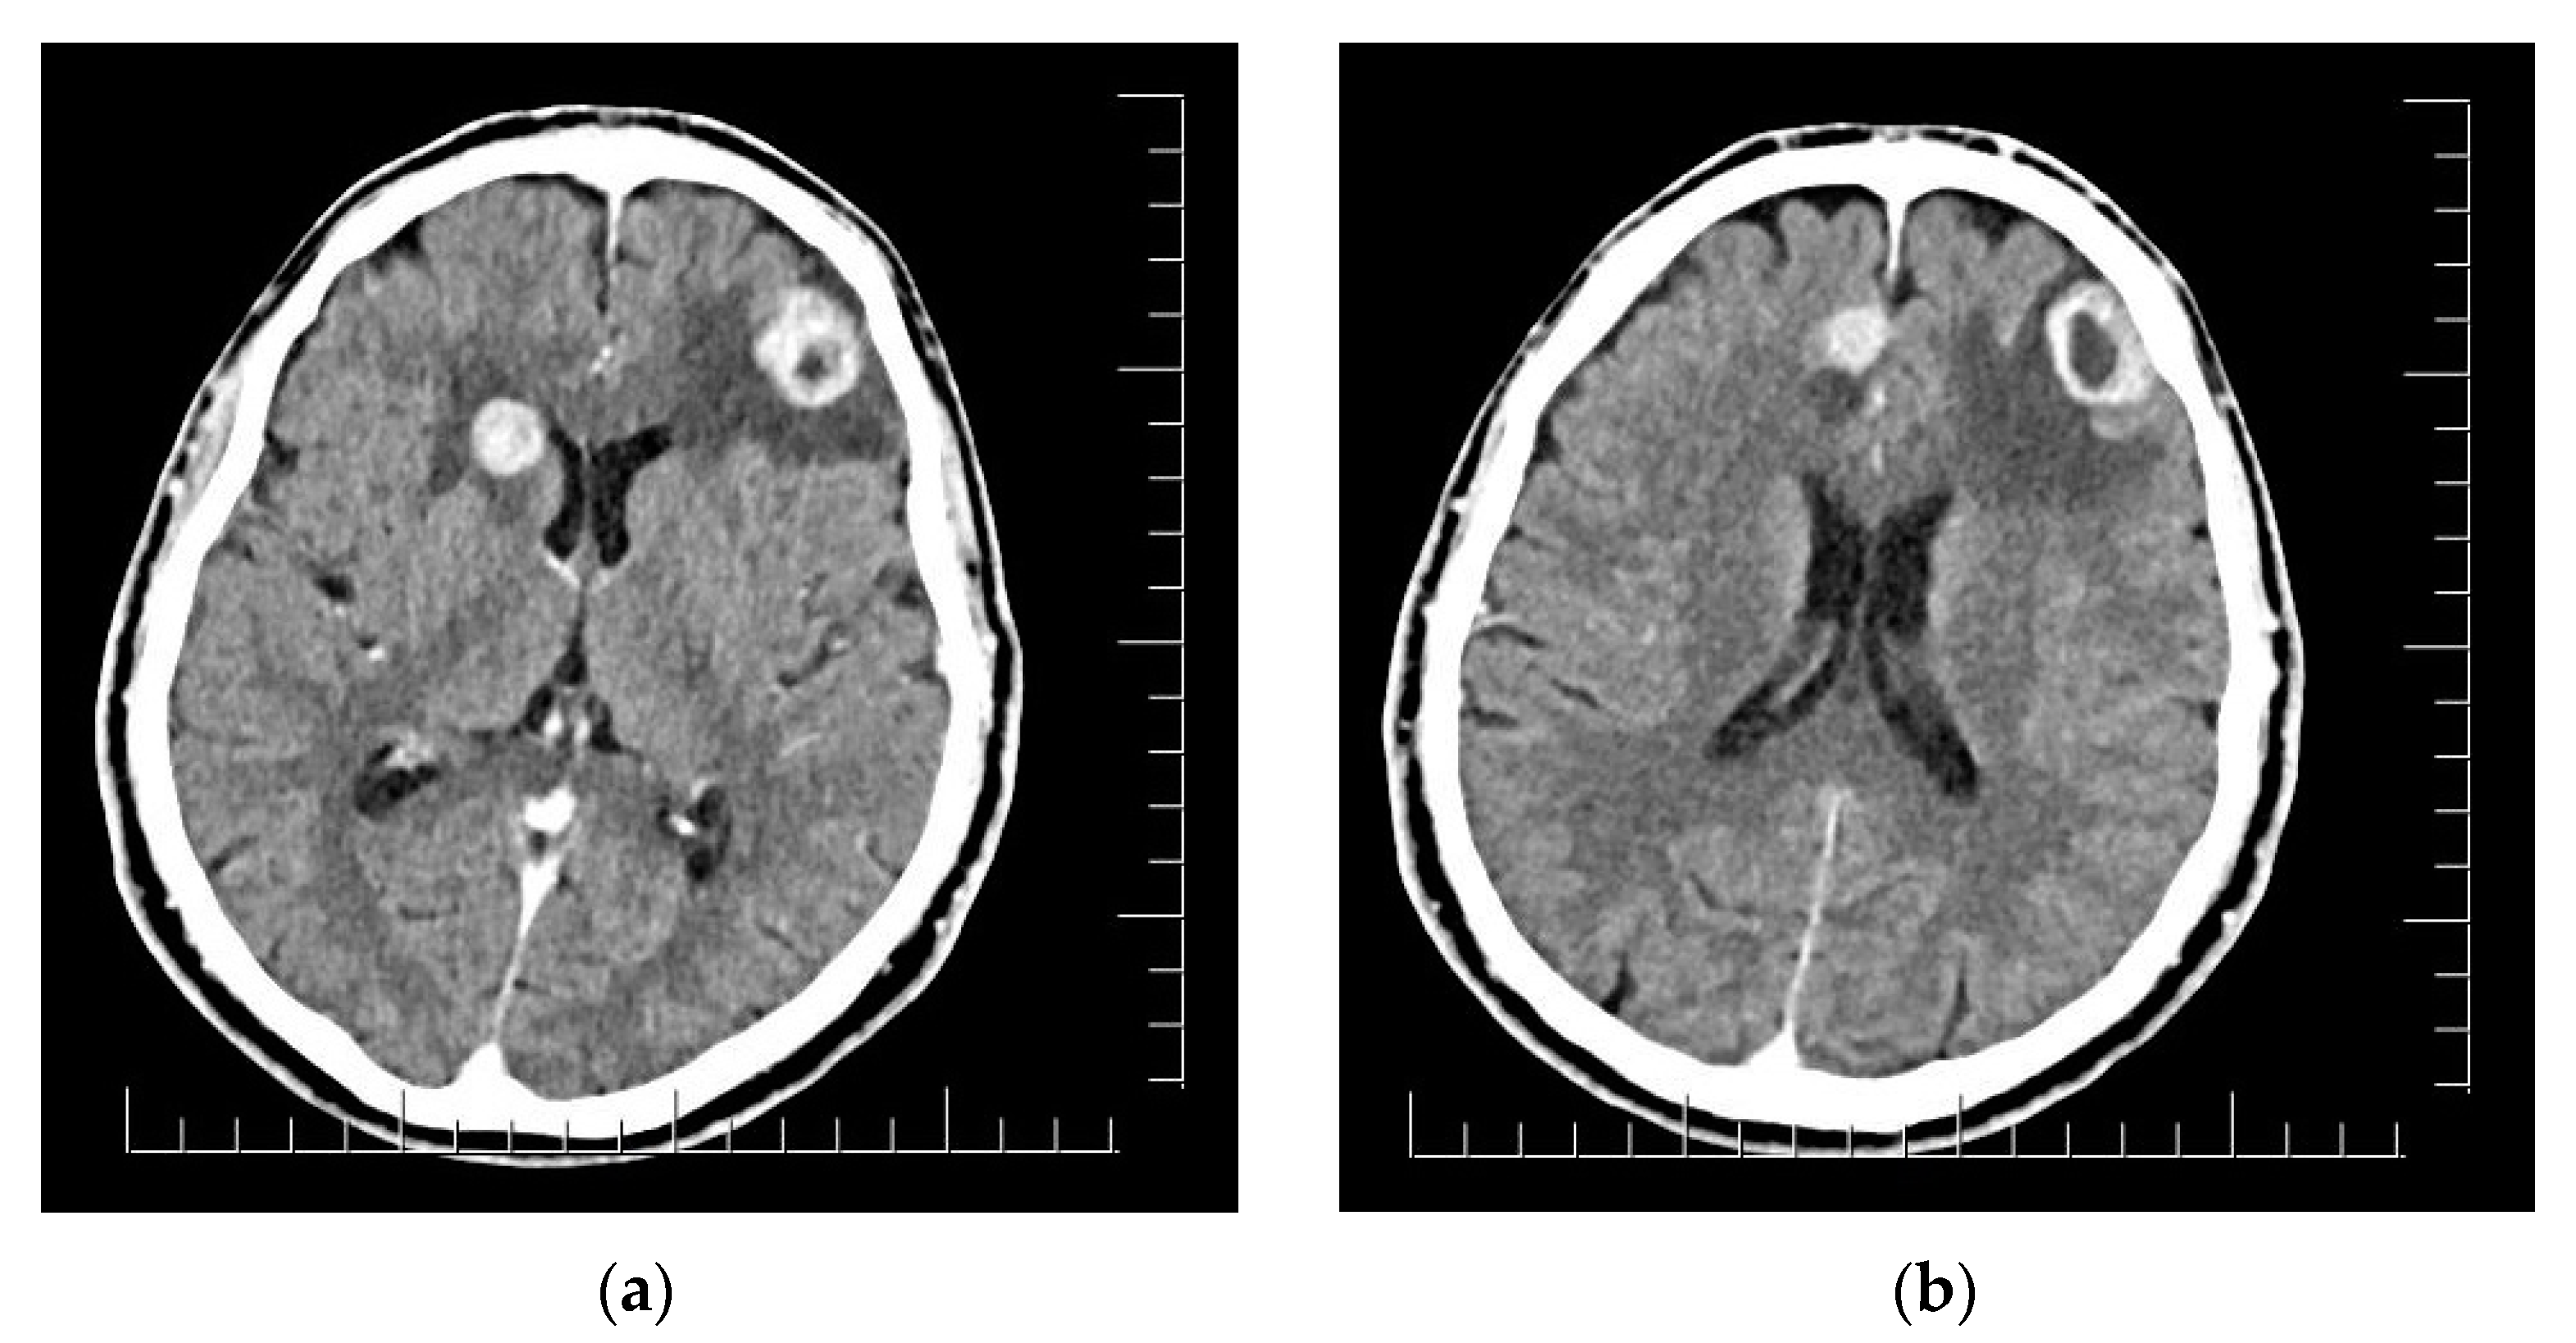

2. Case Presentation